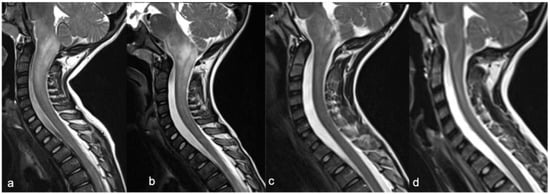

- Rossi, A.; Martinetti, C.; Morana, G.; Severino, M.; Tortora, D. Diagnostic approach to pediatric spine disorders. Magn. Reson. Imaging Clin. N. Am. 2016, 24, 621–644. [Google Scholar] [CrossRef] [PubMed]

- Vargas, M.I.; Delattre, B.M.A.; Boto, J.; Gariani, J.; Dhouib, A.; Fitsiori, A.; Dietemann, J.L. Advanced Magnetic Resonance Imaging (MRI) Techniques of the Spine and Spinal Cord in Children and Adults. Insights Imaging 2018, 9, 549–557. [Google Scholar] [CrossRef]

- Liu, X.; Tian, W.; Chen, H.; LoStracco, T.A.; Zhang, J.; Li, M.Y.; Germin, B.; Wang, H.Z. Advanced neuroimaging in the evaluation of spinal cord tumors and tumor mimics: Diffusion tensor and perfusion-weighted imaging. Semin. Ultrasound CT MRI 2017, 38, 163–175. [Google Scholar] [CrossRef] [PubMed]